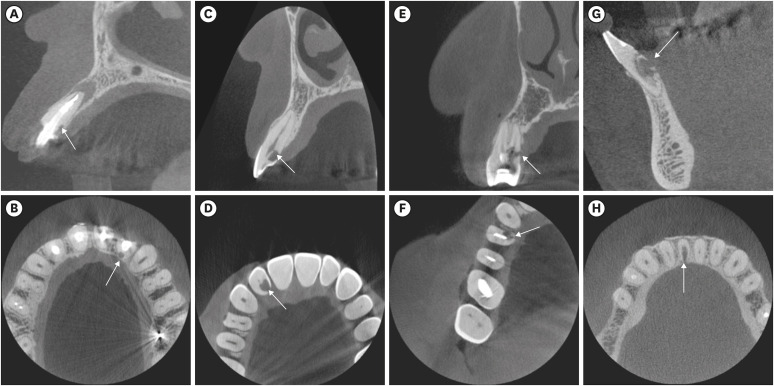

The ECR cases were also evaluated regarding the portal of entry (buccal, lingual/palatal, or proximal) (Figure 3).

Figure 3

Examples of the portal of entry of external cervical resorption lesions indicated by white arrows. (A) buccal, (B) proximal, (C) palatal.

For the portal of entry, 44% of the cases were on the proximal surface, whereas 40.5% were on the lingual/palatal surface, and 15.5% were on the buccal surfaces (Table 3). The portal of entry did not show an association with the type of tooth (p = 0.296).

The portal of entry is the initiation point of resorption and, for ECR to be initiated, the cementum and periodontal ligament should be damaged or absent [22]. Its evaluation is of importance to the treatment plan. In our study, most ECRs were located at the proximal or lingual/palatal surfaces. Matny et al. [5] found a prevalence of 42% at the lingual/palatal portal of the entry surface, which is very similar to our results. Resorptive defects initiated on the lingual/palatal surface are considered difficult to access and therefore might not be possible to treat [5].